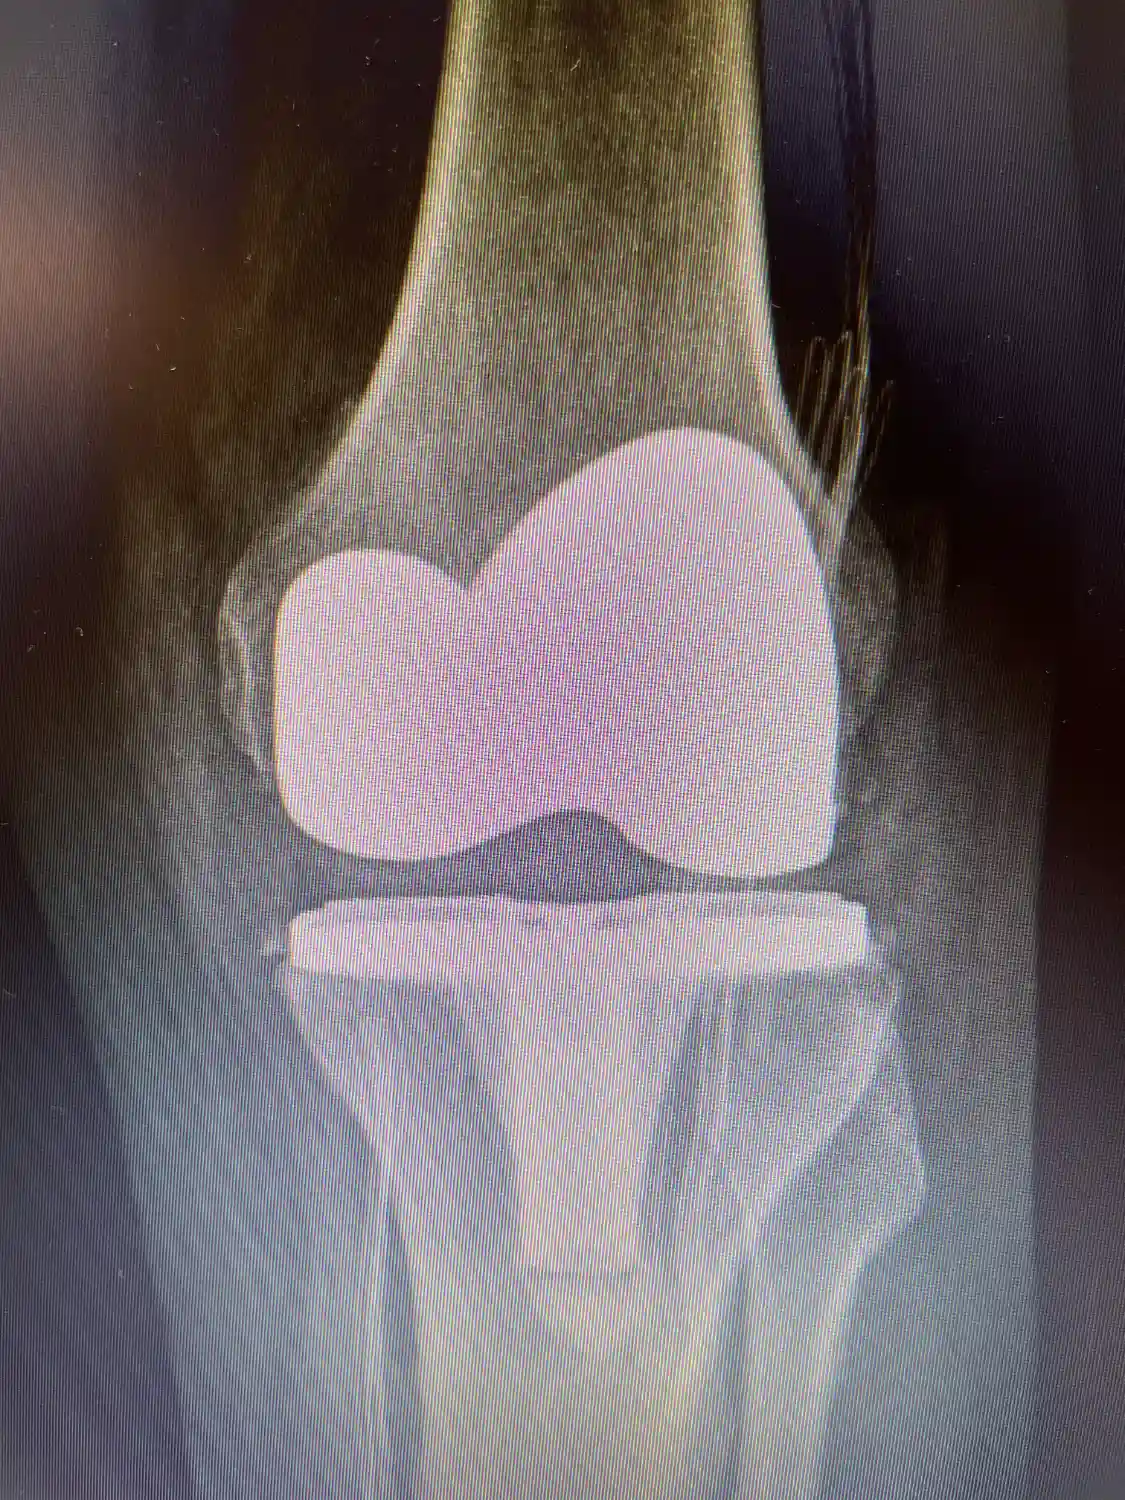

Pós-operatório de prótese de joelho